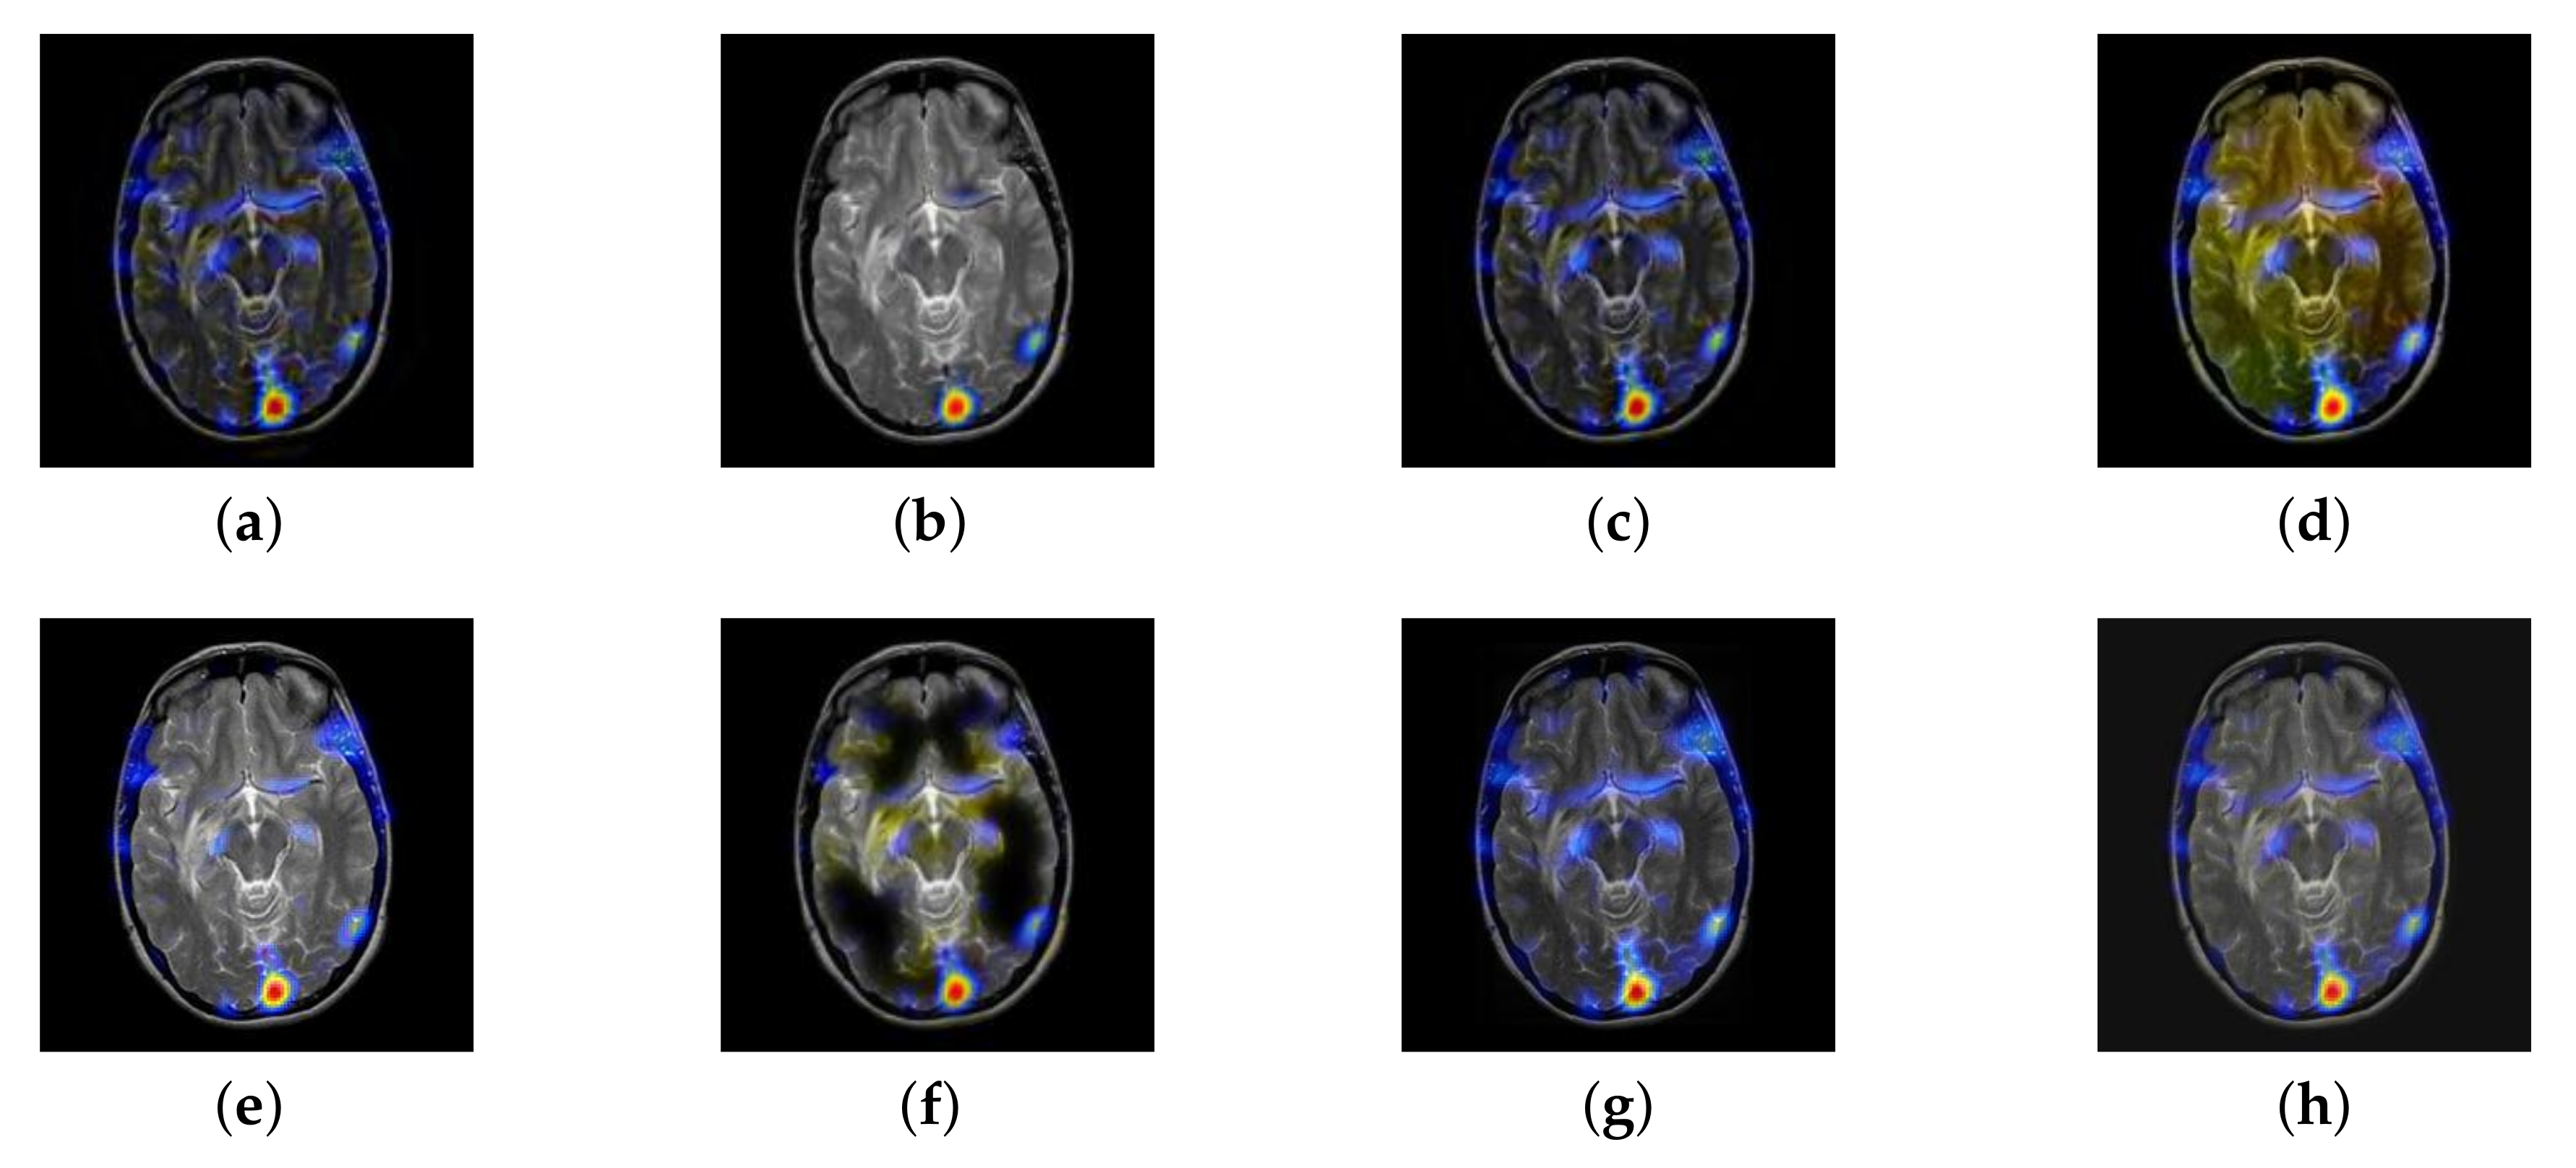

From Figure 12 and Figure 13, we find that algorithm obtains the greatest preference, indicating that FusionNet can get better fusion results from the subjective aspect. The objective evaluation metrics of fused images of all methods in the MRI-SPECT image fusion are shown in Figure 14, Figure 15, Figure 16, Figure 17, Figure 18, Figure 19, Figure 20, Figure 21, Figure 22 and Figure 23. Our FusionNet performs well on SSIM, , , and VIF in MRI and SPECT fusion images. In terms of EN, CE, AG, and FMI, our algorithm is slightly inferior to DDcGAN, IGM, GFF, and FusionCNN. As for the remaining two indicators, our algorithm is similar to other algorithms. Subjective evaluation and objective evaluation are inconsistent sometimes; however, in medical diagnosis, objective evaluation cannot be a complete basis for diagnosis, while subjective evaluation is often more comprehensive. However, the fusion images got by FusionNet have achieved good results in subjective and objective evaluation.

Figure 25.

Fused medical images obtained by different algorithms (Figure 24a,b): (a) DTCWT, (b) GFF, (c) NSCT, (d) LPSR, (e) IGM, (f) FusionCNN, (g) DDcGAN, and (h) FusionNet.

Figure 26.

Fused medical images obtained by different algorithms (Figure 24c,d): (a) DTCWT, (b) GFF, (c) NSCT, (d) LPSR, (e) IGM, (f) FusionCNN, (g) DDcGAN, and (h) FusionNet.